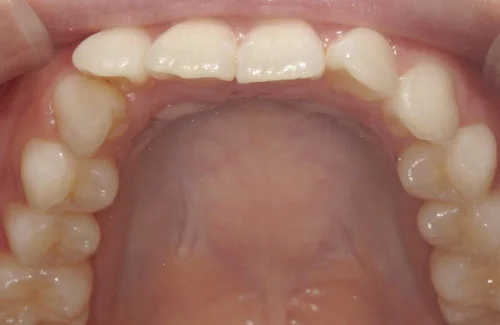

<症例3>前歯のクロスバイトでお悩み

右上の前歯2本が反対に咬合している、いわゆるクロスバイトが主訴でご来院なさいました。

主訴以外の部分には大きな叢生はなく、また患者様も装着時間をしっかり守ってくださったので約6ヶ月で改善することができました。

患者様と症状

主訴:上の前歯が出ている

性別・年齢:20代女性

問題点:上顎左側側切歯のクロスバイト、叢生

診断:前歯部の叢生を伴うアングルⅠ級の不正咬合

主なリスク:矯正中一時的に咬合しにくくなる、歯肉退縮

症状:叢生(そうせい) 上顎前突(じょうがくぜんとつ)

治療内容

治療期間:6ヶ月

治療費用:495,000円(税込)

プラン:14枚コース/ライトプラン

抜歯:親知らずのみ抜歯

再診治療費:無し

追加治療費:無し

保定装置費:無し

治療前後の写真

・2本の前歯が前突しておりましたが、矯正で自然な歯並びになりました。

・前歯の1本が下の歯の裏側に噛み合うクロスバイトになっていましたが、矯正で改善されました。